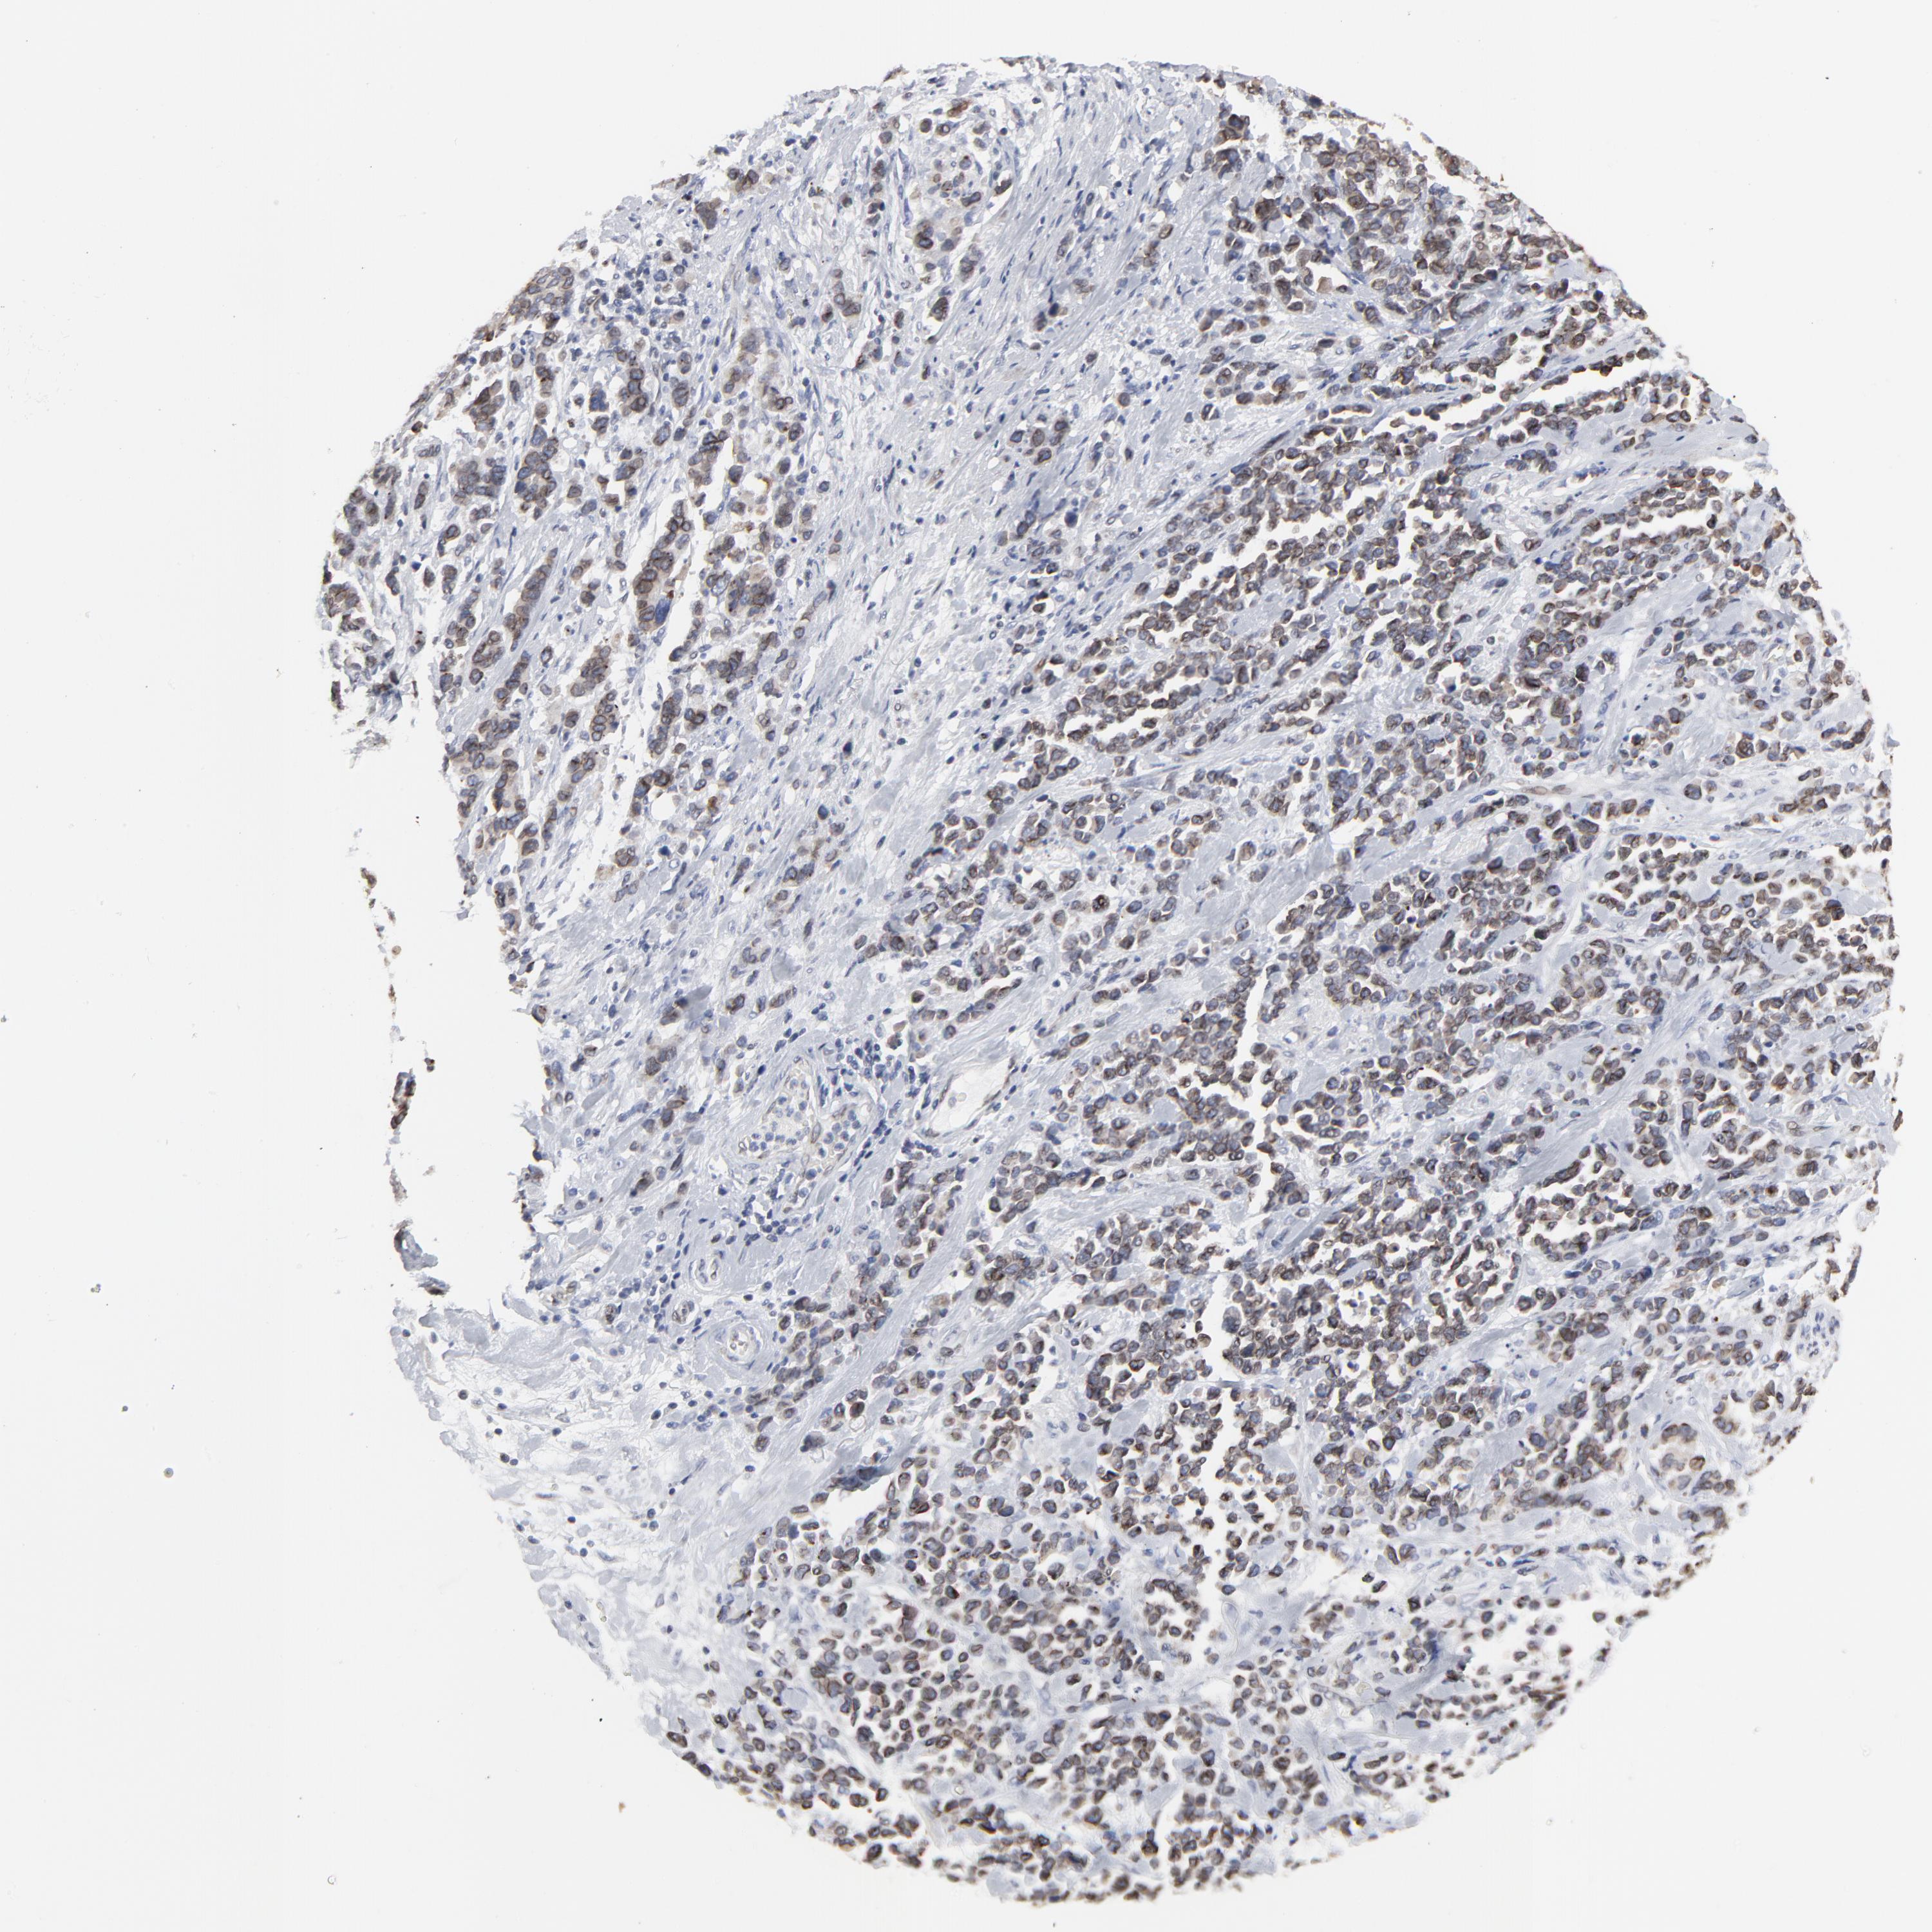

STOMACH CANCER - Protein expressioni

A mouse-over function shows sample information and annotation data. Click on an image to view it in a full screen mode. Samples can be filtered based on level of antibody staining by selecting one or several of the following categories: high, medium, low and not detected. The assay and annotation is described here.

Note that samples used for immunohistochemistry by the Human Protein Atlas do not correspond to samples in the TCGA dataset.

Antibody stainingi

Antibody staining in the annotated cell types in the current human tissue is reported as not detected, low, medium, or high, based on conventional immunohistochemistry profiling in selected tissues. This score is based on the combination of the staining intensity and fraction of stained cells.

Each image is clickable and will lead to virtual microscopy that enables deeper exploration of all samples and also displays staining intensity scores, fraction scores and subcellular localization as well as patient and tissue information for each sample.

Antibody HPA003435

Antibody HPA050204

Staining

High

Medium

Low

Not detected

Intensity

Strong

Moderate

Weak

Negative

Quantity

>75%

75%-25%

<25%

None

Location

Nuclear

Cytoplasmic/membranous

Cytoplasmic/membranous,nuclear

Adenocarcinoma, NOS